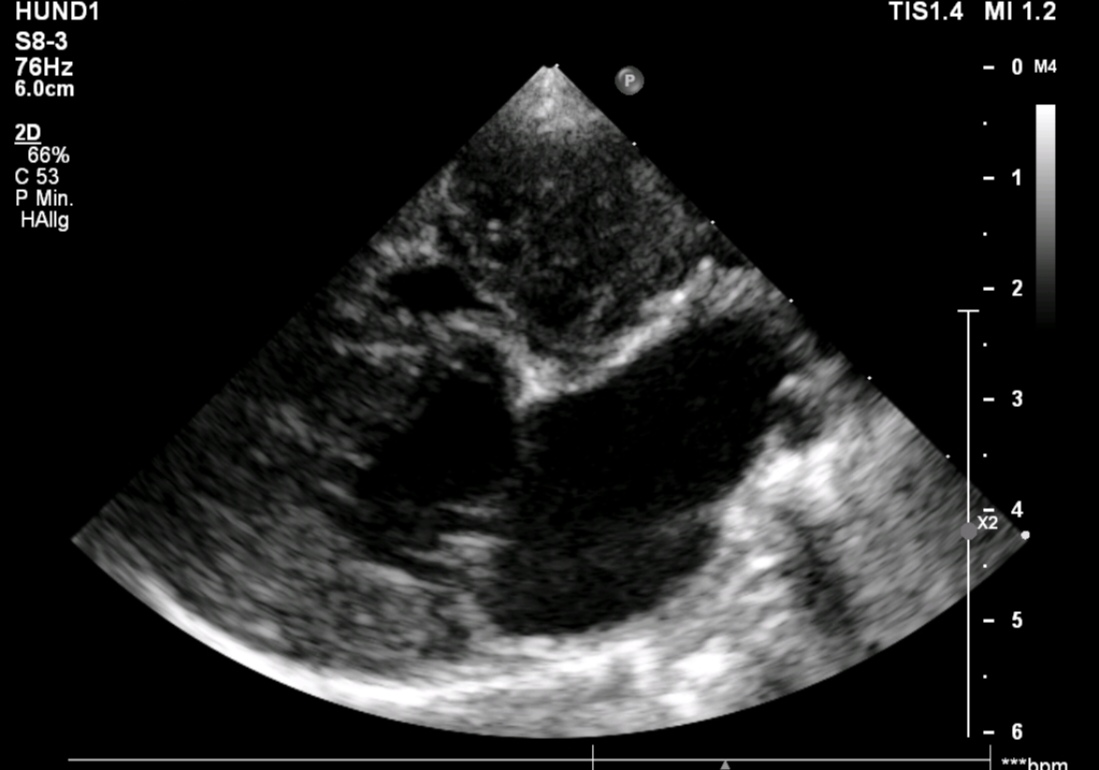

Chihuahua „Peppi“ sollte vor einer anstehenden Zahnsanierung noch mal seine bekannte Mitralendokadiose, sprich Herzklappenerkrankung, gecheckt bekommen. Doch was Frau Dr. Eulitz entdeckte, hatte leider mit dem Vorbefund nichts mehr zu tun. In Peppis rechtem Herzen war ein Tumor gewachsen. Obwohl dieser die rechten Herzanteile deutlich komprimierte und sogar ein leichter Perikarderguss vorlag, war Peppi für seine 13Jahre erstaunlich fit.